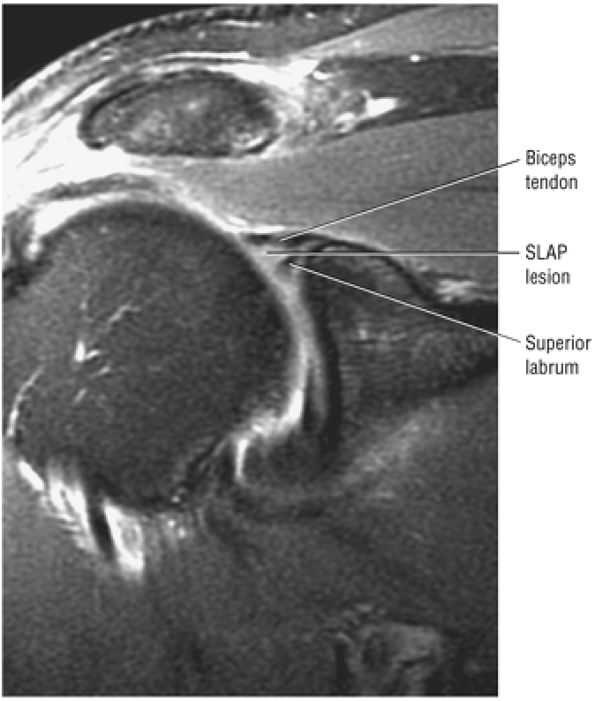

Type 2 SLAP tear extending primarily into the posterior superior labrum